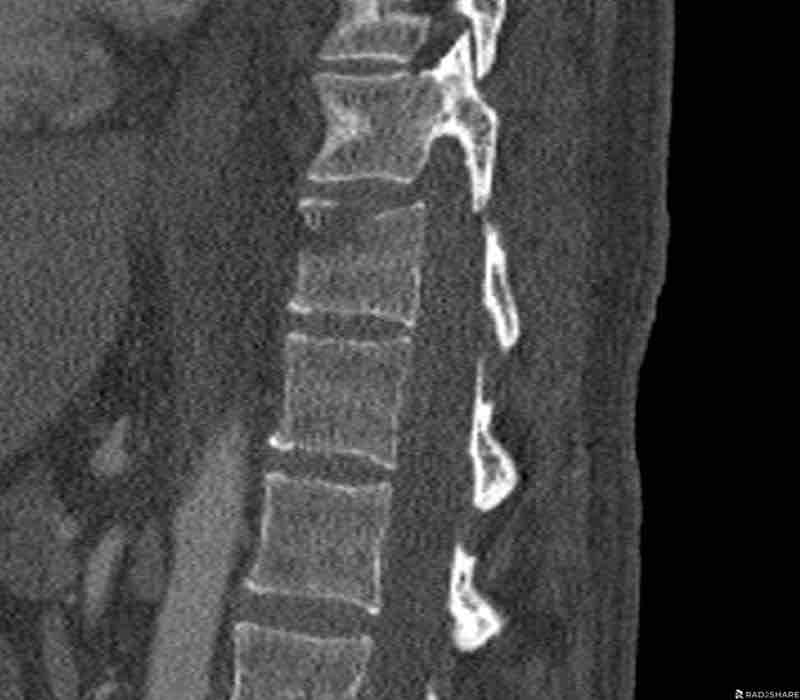

Scroll through images.

What are the findings?

Findings

- C injury? No.

- Signs of a rigid spine?

Yes (DISH), so a B3 injury is very likely. - A subtle fracture on the anterior vertebral body (arrows).

- No separation, probably due to positioning of patient in the scanner

Conclusion

Injury type B3.